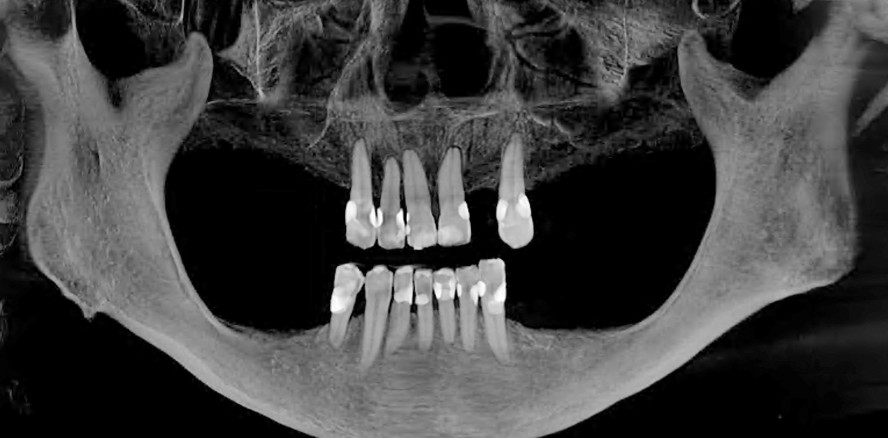

Heutzutage gibt es immer noch viele Patienten, die in der Folge von Zahnextraktionen signifikant Knochenvolumen verloren haben und bei denen deshalb Knochenaufbaumaßnahmen erforderlich sind. Im folgenden zweiten Teil der Artikelreihe werden sechs weitere besondere Maßnahmen mit Schwerpunkt auf der Verwendung von autologen Materialien skizziert, bevor ein abschließendes Fazit gezogen wird.

Knochen von Lebendspendern wird verwendet, wenn die Restknochenhöhe geringer als 3 mm ist oder große Perforationen im Alveolarkamm vorliegen (Abb. 2a und b). Wie man an dem hier dargestellten Beispiel erkennen kann, hat nach bereits vier Monaten gut vaskularisierter Knochen den Spenderknochen praktisch vollständig ersetzt (Abb. 3a–g).